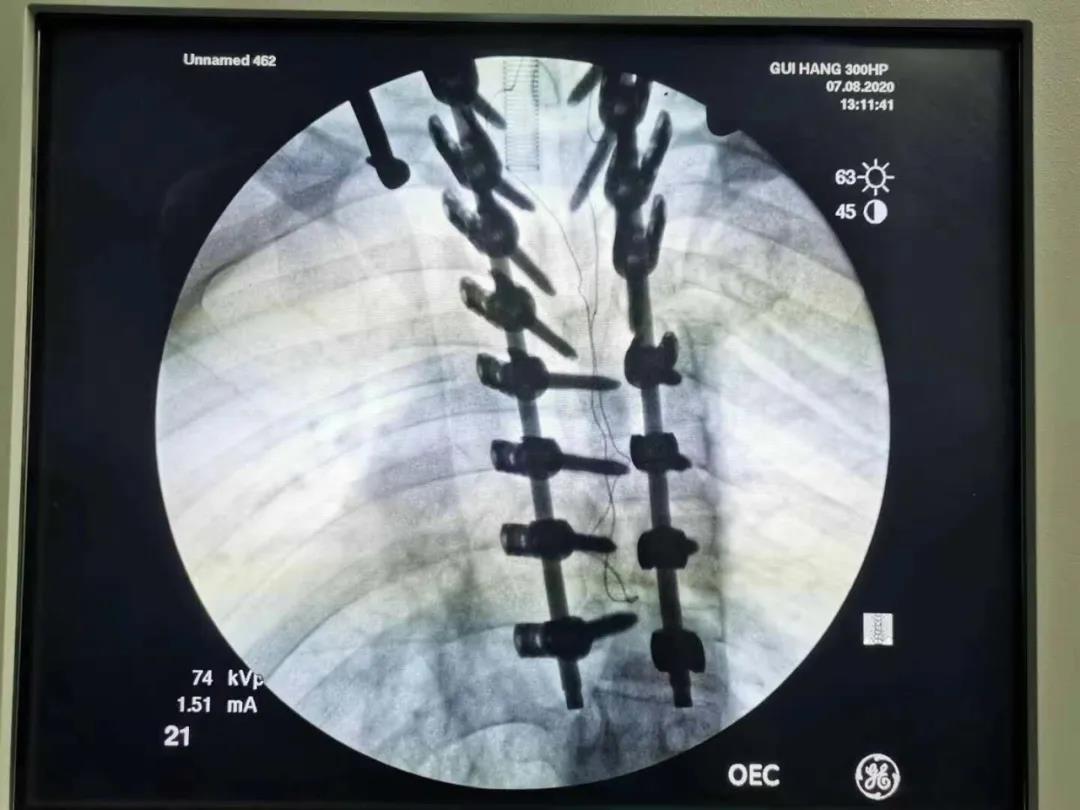

8月7日,在手术麻科医护人员的全力配合下,医生为张某做了经后路脊柱松解矫形,椎弓根螺钉内固定术。术中,医生对患者的四肢神经进行全程检测,最终历时7个小时成功完成手术。

手术后,预计脊柱变直的张某身高将从1.55米长到了1.60米,足足高了5厘米。目前,他还在医院接受后续治疗。